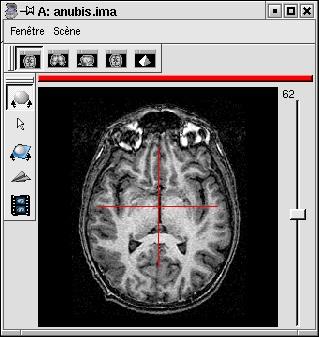

If your image is not spatially normalised, Anatomist will help you to click on the 3 or 4 points of interest.

- If the volume is not already visible, click on the edit button of one of the point parameters to have Anatomist display it

- Set the Anatomist view so as to see the point (use the slice slider) and click in it on the wished point.

- When the cursor position is good, click on the button of the 3D point in BrainVISA: the position is transfered from Anatomist to BrainVISA.

- If you are not happy with the position, you can restart the operation: click again on other points then on the parameter button to validate: a new position replaces the previous one in BrainVisa.

You have to select 3 points (you can use a sagittal slice if you prefer):

- Intersection of anterior commissure with interhemispheric plane;

- Intersection of posterior commissure with interhemispheric plane;

- Any point of the interhemispheric plane not aligned with the previous ones.

- Optionally, any point of the left hemisphere. Specifying this point is not mandatory, it is only useful to detect a possible orientation problem on the input image. Be careful, axial and coronal views in Anatomist are in radiological convention by default (left and right are flipped).

Anterior commissure: